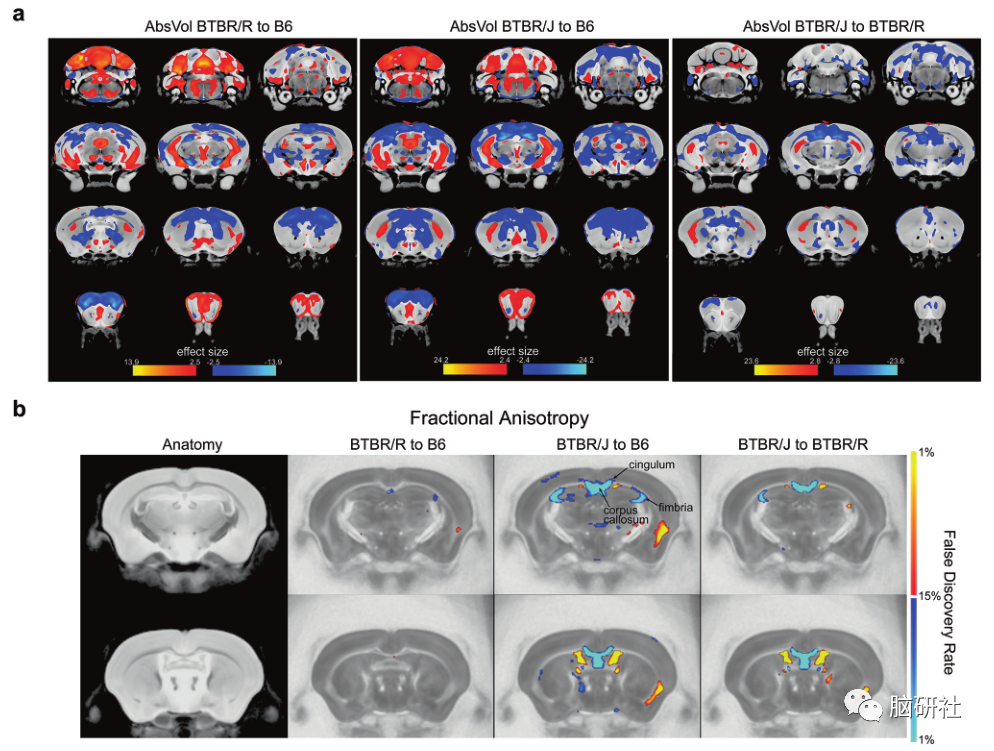

BTBR/R和BTBR/J具有显著的解剖学差异和不同的白质模式研究结果显示,BTBR/J和BTBR/R小鼠在包括杏仁核在内的33个区域存在差异。尽管BTBR/J的胼胝体受损,但BTBR/R的胼胝体是正常的。研究人员发现,与正常小鼠相比,BTBR/R小鼠的内源性逆转录病毒(ERV)水平显著增加。此外,实时荧光定量PCR检测方法显示这些逆转录病毒在BTBR/R小鼠中被激活。另一方面,在正常小鼠中,在相同的重复序列中分类的表达却没有变化,表明这种逆转录病毒激活对BTBR具有特异性。在研究中,研究人员从行为学层面全面考察了BTBR/J和BTBR/R的差异。与BTBR/J小鼠相比,BTBR/R小鼠的焦虑程度较低,并且在超声发声方面表现出定性变化,这是一种评估小鼠沟通能力的方法。BTBR/R小鼠也表现出更多的自我理毛行为,并且在大理石掩埋测试中埋了更多的大理石。这两个测试旨在检测自闭症个体的重复性行为异常。研究结果表明,BTBR/R比BTBR/J表现出更多的重复行为(即症状性更强)。衡量一只老鼠接近另一只老鼠的程度的实验结果也显示,BTBR/R小鼠比BTBR/J小鼠有更明显的社会缺陷。此外,利用巴恩斯迷宫进行空间学习测试,BTBR/J小鼠的学习能力低于正常小鼠。另一方面,BTBR/R小鼠表现出与正常小鼠相似的能力。